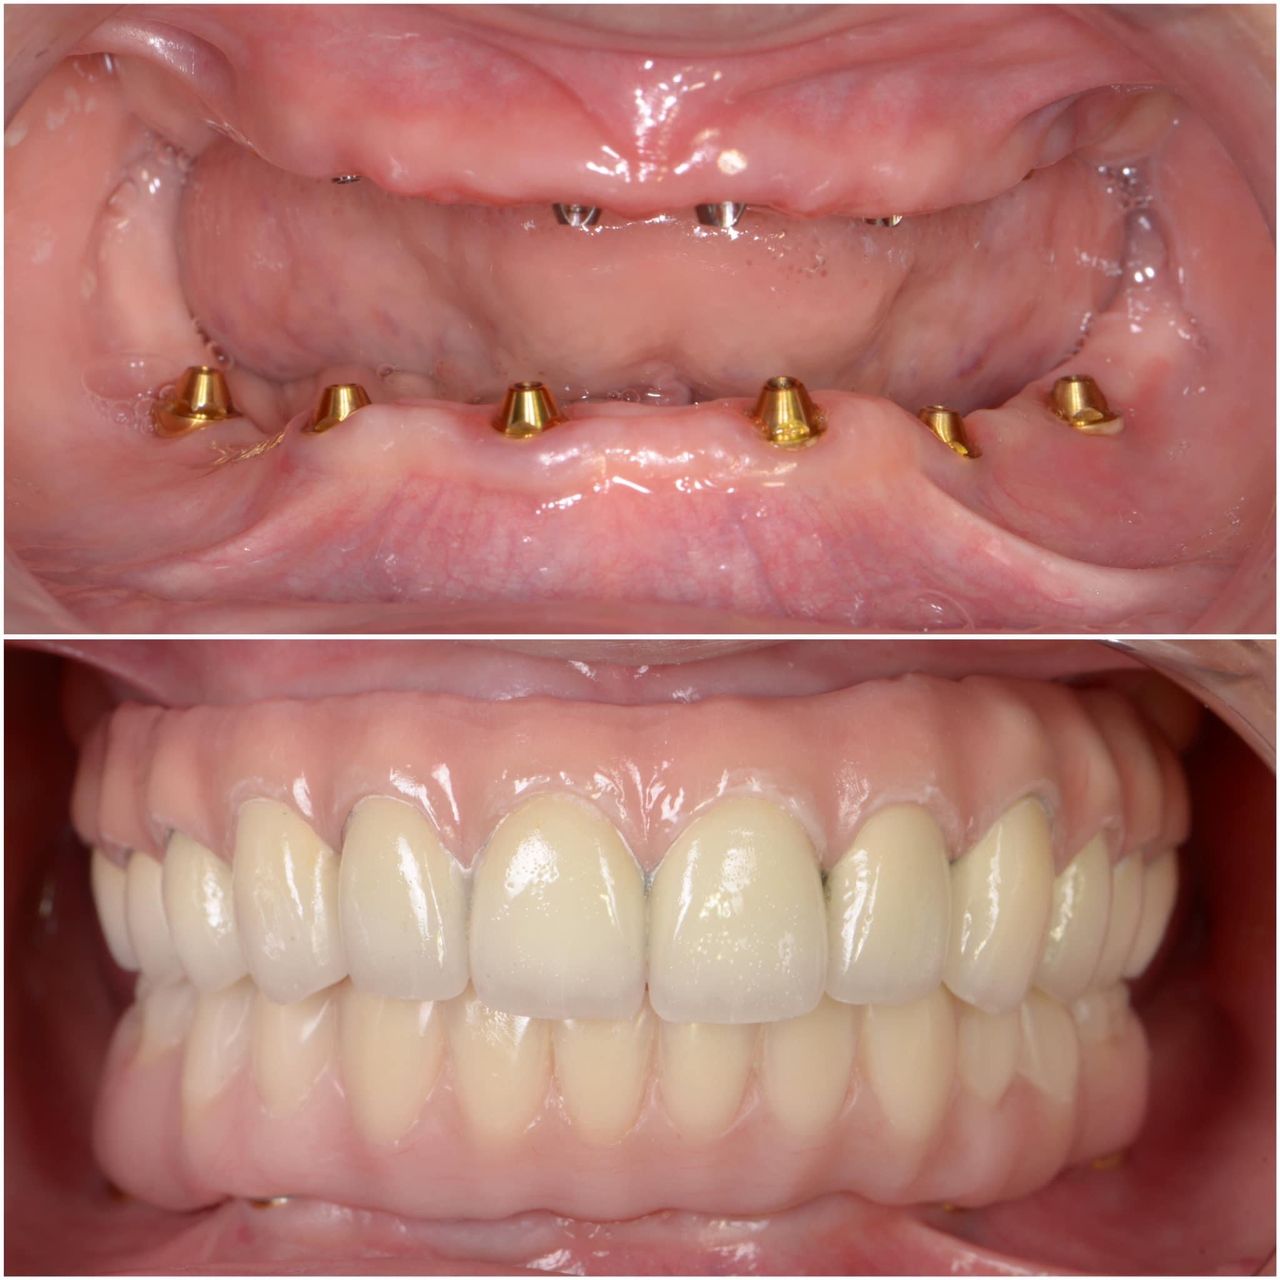

Contamos con odontología digital de vanguardia que nos permite realizar diseños de sonrisa personalizados, tratamientos de alineación dental mediante alineadores como alternativa a la ortodoncia convencional, así como la colocación de coronas y carillas de porcelana, fundamentales para lograr una sonrisa estética, armónica y funcional.

La realización de coronas dentales debe ser exclusivamente por un experto.La corona dental da protección y estética a un diente, no siempre requiere de tratamiento de endodoncia, solo en algunas ocasiones. El procedimiento requiere de mucha precisión para lograr una corona dental perfectamente bien sellada, de acuerdo a los mas recientes artículos científicos 8 de 10 coronas no sellan a la perfección.Anteriormente se realizaban coronas de metal con porcelana las cuales al cabo de un tiempo cambiaban de color y presentaban corrosión en el diente, en la actualidad contamos con diversos tipos de coronas realizadas por medio de CAD CAM zirconia, porcelana y otros materiales de alta calidad.